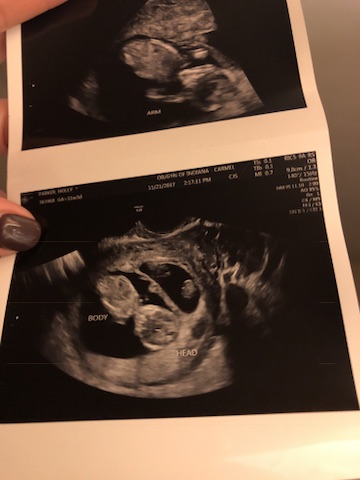

I always knew I wanted to be a mother. I always have known I wanted a big family. My dream has always been to have children. I wanted the picture perfect layout of life. Find an amazing man, get engaged, have a fairy tale wedding (totally did–that’s a whole other post), and then start a family. Just over 3 months into my marriage, I found out I was pregnant. We were so excited, but also a little terrified of what was to come (normal right?). Anxiously awaiting the coming couple of weeks before we had our first ultrasound, we told our closest family and friends (we could not keep that secret), by sending them a little picture of some alfredo & pregnancy test. At my eight week ultrasound, we were excited to see our little gummy bear of a baby, and hear the heartbeat. We were filled with nerves when the ultrasound tech said, “Wait a minute…” Umm.. WHAT. Never tell an expecting momma to “wait” without telling her why. It was a few minutes (felt like an hours) that passed when she asked if twins ran in my family… “No… WHY?” Because she found Baby A, and a Baby B. My eyes swelled with tears (excitement, fear, a little… What the HECK?!). Adam was beaming with happiness. Our amazing doctor, told us we had two very strong heartbeats, and to prepare for a life with twin babies. We left that ultrasound with a whole new expectation of this pregnancy. The coming weeks I did everything I was supposed to do as an expecting momma– ate all the right foods, took my prenatal and folic acid, plenty of sleep, etc. We were excited to see our sweet babies at our next ultrasound at 12 weeks. At the routine appointment, we were shocked to see that there was no growth in Baby A. There also was no heartbeat. Devastation was an understatement. I felt like I had failed as a mother… “What did I do wrong??” was all I thought… I felt no physical pain, no bleeding, nothing out of the “norm.” How could this of happened??? I couldn’t even look at the screen due to being so upset about having lost one of my babies… (Que guilt of not “caring” about the other healthy baby that was THRIVING). My emotions had complete control of me. I was in a whirlwind… So upset over having lost my baby, but felt lucky that I still had a healthy baby thriving inside. I can’t even imagine the pain, the horror, the guilt of if I had lost both. My heart still sinks when reliving that day, and even thinking about the thousands and thousands of mommas who have gone through miscarriage. There was no explanation as to why this happened other than it was probably just a chromosomal disfunction or one of the babies (Baby B) was taking more nutrients than the other. That was hard for me to swallow.. the WHY. After my grief period, I picked myself up and was able to thank God for giving me the opportunity to still nurture the strong baby I still had. I decided that there was a greater reasoning behind the “WHY,” and I was going to “give it to God.”